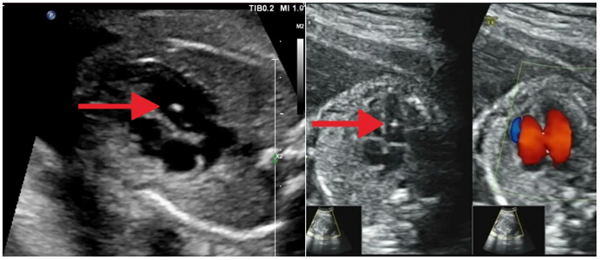

信号一:心室强光点——心脏里的“小星星”

B超单提示:“左/右心室腔内可见一强光点”

它是什么?可以理解为心脏肌腱上的一个微小钙化点,像照片里的一个“光斑”。

医生解密:

1.这种情况十分常见,在孕中期排畸B超中,尤其在亚洲宝宝中,这是个普遍现象。

2.孤立=安全:如果只有这一项异常,且NT、无创DNA等都正常,那它基本没影响,可以把它看作一种正常的“声像图变异”。

3.会自己消失:绝大多数强光点在孕晚期会自行缩小或消失,不影响心脏功能。

4.何时要警惕?只有当它合并了其他多项异常指标时,医生才会建议深入检查。